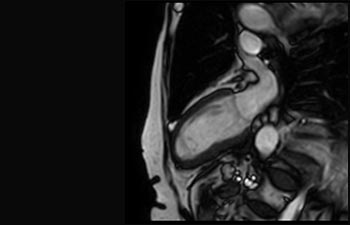

Sehen Sie selbst, was die ersten Nutzer von Ingenia Prodiva 1.5T über ihre Erfahrungen mit dem System und dessen Auswirkung auf ihre radiologische Praxis berichten.

Die richtige Geschwindigkeit bei jeder Untersuchung.

Finden Sie die richtigen klinischen Applikationen für Ihre Anforderungen